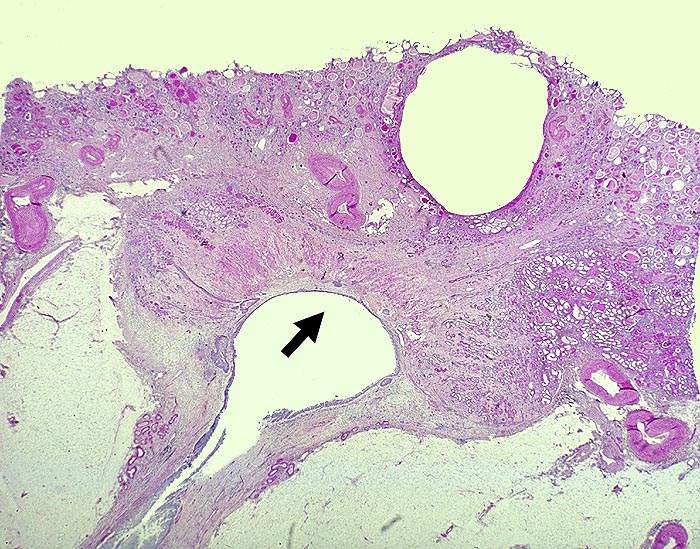

AP/ Analgetikanephropathie

Analgetikanephropathie

Niere

Morphologie